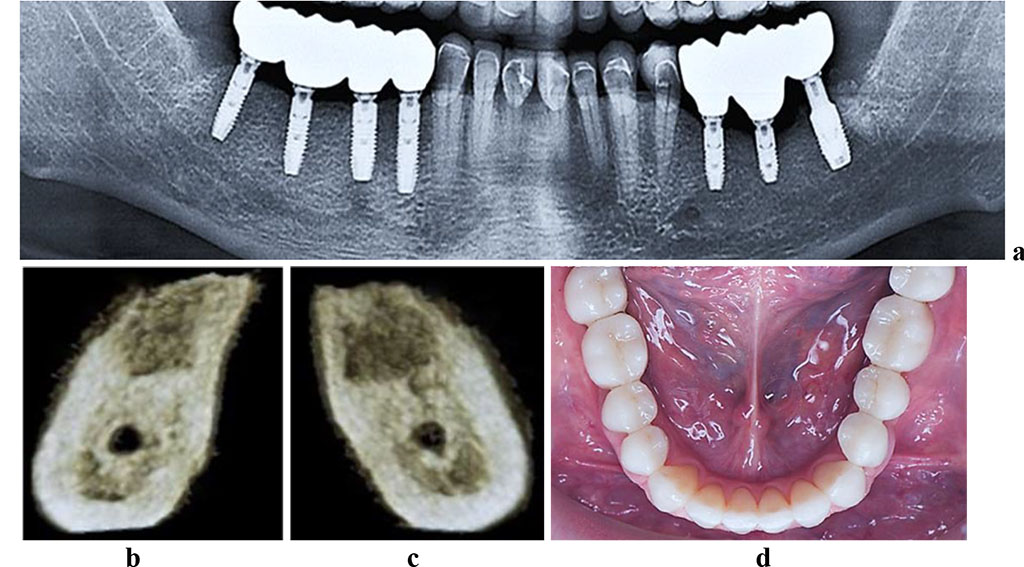

The CBCT of the cross-sectional 3D window at the area of planned dental implantation in the main group revealed minor changes in the bone tissue microarchitectonics, while the amount of bone was maintained. The 3D window of volumetric rendering mode showed that at the area of dentition defects, the cortical bone was wide and intact throughout. There were some minor qualitative changes observed in the spongy bone: the spongy bone trabeculae width and the bone trabeculae structure density were slightly reduced; there were some spots identified where the intertrabecular space was expanded; the vestibular and lingual cortical plates were intact; the trabecular structure preserved its integrity yet there was a slight change in the structure arrangement (disorientation) observed in the bone trabeculae (Fig. 6-8).

Figure 7. Patient R., 51 y.o. Diagnosis: lower jaw partial adentia; Class III by Kennedy. Lower jaw CBCT: a – bone tissue 12 months following the installation of dental implants (panoramic reformat); 3D cross-sections at the adentia area 3.7 (b) and 3.6 (c) prior to the installation of dental implants; d – lower dentition after implantological and prosthetic treatment.